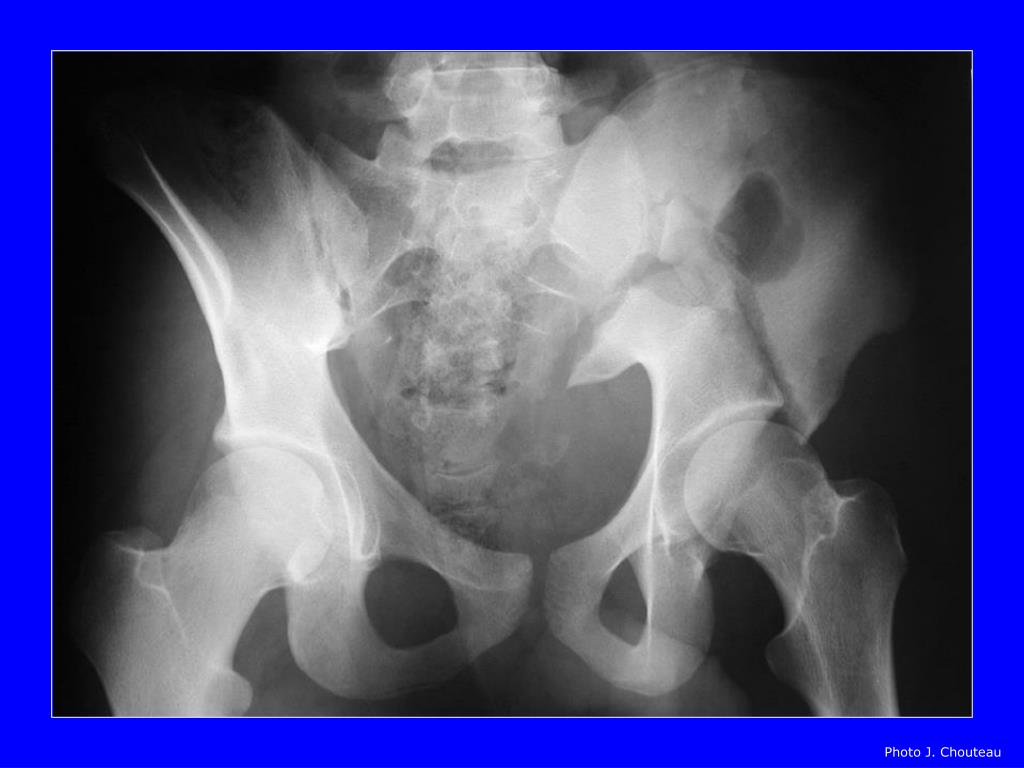

Fracture De Bassin . Le bassin est constitué de 3 structures osseuses : Dans cet article, on vous dit tout sur les fractures du bassin. Les fractures du bassin du sujet mûr, touchant plus volontiers les femmes, en raison de l'ostéoporose, et qui. Accident de voiture, de deux roues, chute violente, ou simplement de sa. L’iliaque, le sacrum et le pubis. Une rupture osseuse très douloureuse. Définition et types de fracture du bassin. Les fractures du bassin constituent la 3ème cause de mortalité lors d’accidents de la voie publique et ne sont précédées que par les traumatismes. | quelles sont les causes d’une fracture du bassin ? Il existe trois grandes catégories de fractures du bassin suivant le contexte : | quels sont les symptômes d’une fracture du bassin ?

| quelles sont les causes d’une fracture du bassin ? Les fractures du bassin constituent la 3ème cause de mortalité lors d’accidents de la voie publique et ne sont précédées que par les traumatismes. Le bassin est constitué de 3 structures osseuses : Une rupture osseuse très douloureuse. Les fractures du bassin du sujet mûr, touchant plus volontiers les femmes, en raison de l'ostéoporose, et qui. Définition et types de fracture du bassin. | quels sont les symptômes d’une fracture du bassin ? Accident de voiture, de deux roues, chute violente, ou simplement de sa. Il existe trois grandes catégories de fractures du bassin suivant le contexte : Dans cet article, on vous dit tout sur les fractures du bassin.

Fracture De Bassin Les fractures du bassin constituent la 3ème cause de mortalité lors d’accidents de la voie publique et ne sont précédées que par les traumatismes. Accident de voiture, de deux roues, chute violente, ou simplement de sa. | quels sont les symptômes d’une fracture du bassin ? Le bassin est constitué de 3 structures osseuses : Dans cet article, on vous dit tout sur les fractures du bassin. L’iliaque, le sacrum et le pubis. | quelles sont les causes d’une fracture du bassin ? Il existe trois grandes catégories de fractures du bassin suivant le contexte : Les fractures du bassin constituent la 3ème cause de mortalité lors d’accidents de la voie publique et ne sont précédées que par les traumatismes. Les fractures du bassin du sujet mûr, touchant plus volontiers les femmes, en raison de l'ostéoporose, et qui. Définition et types de fracture du bassin. Une rupture osseuse très douloureuse.